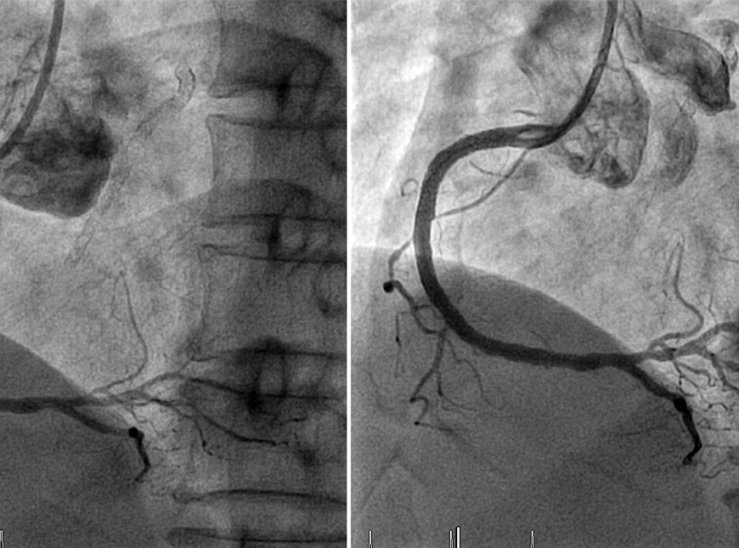

Коронарографія — це рентгенологічне дослідження судин серця. Через невеликий прокол у стегновій чи променевій артерії вводять тонкий катетер, який підводять до коронарних судин. Далі через нього подається контрастна речовина, і під контролем ангіографа лікар бачить повний малюнок артерій на екрані.

Цей метод вважається «золотим стандартом» у діагностиці ішемічної хвороби серця. Жодне інше дослідження — ні ЕКГ, ні УЗД, ні навіть комп’ютерна томографія — не дає настільки повної та достовірної інформації.